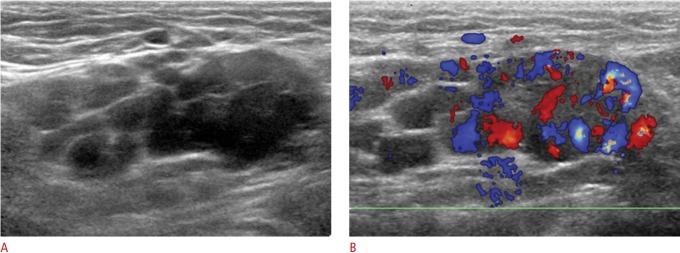

Groin lesions can be classified as neoplastic or non-neoplastic. Neoplastic lesions include lipoma, epidermoid cyst, angiomyofibroblastoma-like tumor, liposarcoma, and synovial sarcoma, as well as metastases from lymphoma, neuroendocrine carcinoma, and carcinomas of the lung, breast, urinary bladder, ovary, vulva, and colon. Non-neoplastic lesions include hernias, round ligament varices, endometriosis, Kimura disease, Castleman disease, hematoma, and inflammation. Because the clinical implications and therapeutic strategies for groin lesions vary depending on the cause, the ability to noninvasively differentiate among etiologies is very important. Although there is substantial overlap in ultrasonographic findings across various groin lesions, some ultrasonographic features, along with clinical characteristics, may suggest a specific diagnosis. Familiarity with the ultrasonographic and clinical features of various groin lesions facilitates accurate diagnosis and treatment.

腹股沟病变可分为肿瘤性或非肿瘤性。肿瘤性病变包括脂肪瘤、表皮样囊肿、血管肌纤维母细胞瘤样肿瘤、脂肪肉瘤和滑膜肉瘤,以及淋巴瘤、神经内分泌癌和肺癌、乳腺癌、膀胱癌、卵巢癌、外阴癌及结肠癌的转移瘤。非肿瘤性病变包括疝、圆韧带静脉曲张、子宫内膜异位症、木村病、卡斯特曼病、血肿和炎症。由于腹股沟病变的临床意义和治疗策略因病因不同而异,因此无创鉴别病因的能力非常重要。尽管各种腹股沟病变的超声表现有很大重叠,但一些超声特征结合临床特点可能提示特定诊断。熟悉各种腹股沟病变的超声和临床特征有助于准确诊断和治疗。